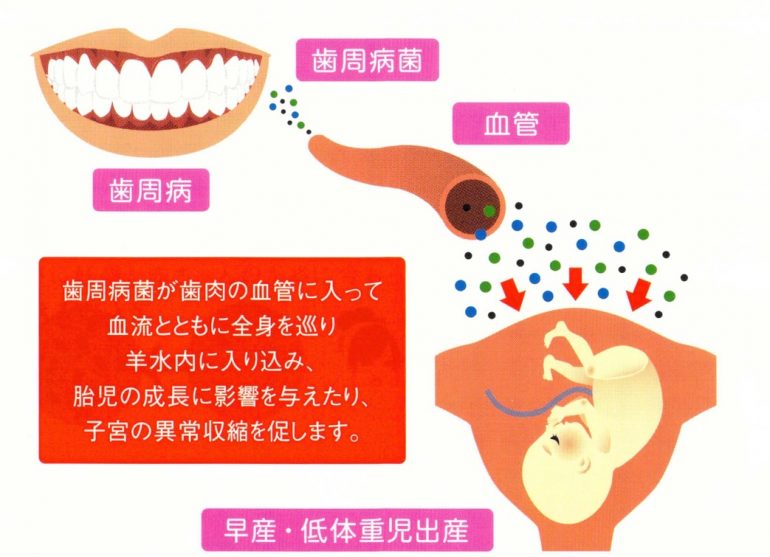

妊娠中や授乳中の方

歯周病菌の殺菌・抑制

歯周病菌は低体重児や早産のリスクを高めるため妊娠中は歯周病菌の殺菌が重要です。